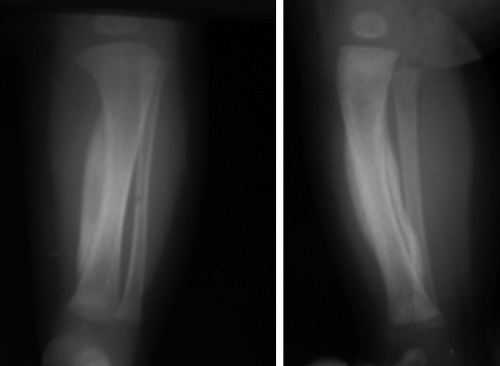

У некоторых больных эта патология возникает резко и не имеет связи ни с одной болезнью. При рентгенисследовании излюбленных мест локализации на конечностях, а также других поврежденных областей тела наблюдается симметричное утолщение диафизарной части, которое образовалось вследствие ровных, гладких периостальных наслаиваний. В последующем последние более уплотняются и соединяются с корковым слоем.